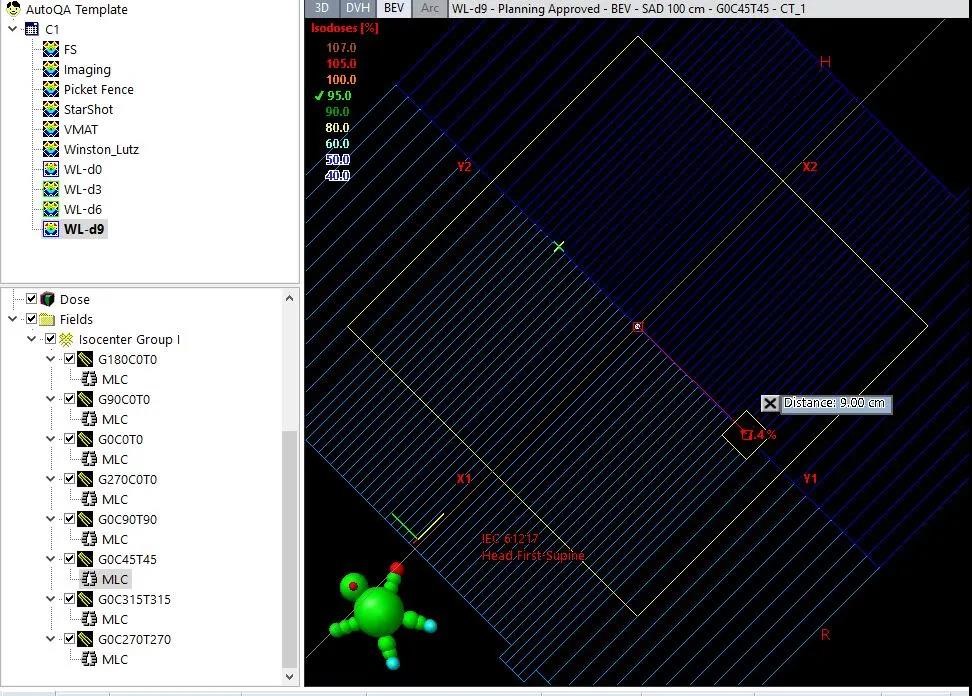

1、Winston-Lutz-Gao Test

一个等中心多靶点照射,难免会出现某些靶点距离等中心较远的情况,这时候我们怎么确保治疗的精度?其中一项很有意义的测试就是设计偏中心照射野进行Winston-Lutz测试。

在偏中心9cm处,开一个2*2cm的小野,

进行Winston-Lutz测试

使用DoseLab分析结果显示,最大误差为0.7mm,

治疗精度完全可以控制在1mm以内